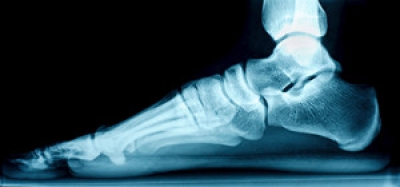

An ankle sprain occurs when the foot twists or rolls in a way that overstretches or tears the ligaments supporting the ankle joint. This often happens during sports, walking on uneven ground, or wearing shoes that lack adequate support. The outer ligaments of the ankle are most frequently injured, leading to pain, swelling, and bruising. In more severe ankle sprains, surrounding tendons or cartilage can also be affected. A podiatrist can perform a physical exam to assess the extent of ligament damage and determine whether the injury involves torn tissue or a fracture. Diagnostic imaging such as X-rays or an MRI may be ordered to confirm the diagnosis and rule out or uncover other injuries. Treatment depends on the severity of the ligament damage and may involve immobilization, supportive devices, or surgery in serious cases. If you believe you have sprained an ankle, it is suggested that you make an appointment with a podiatrist for a diagnosis and treatment.